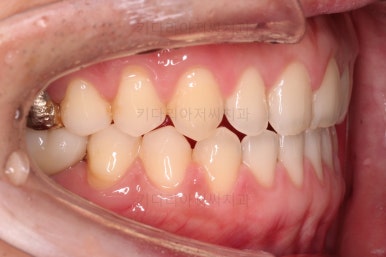

교정장치를 부착하고 충치치료는 별개로 진행되었어요.

이번에 선택하신 장치는 자가결찰(철사를 잡아주는 뚜껑이 자체적으로 달려있는) 메탈(금속)장치이며 엠파워 메탈이라고 하는 장치입니다.

세라믹에 비해 많이 보인다는 단점이 있지만 저렴하고 튼튼한 관리가 약간은 더 편하다는 장점이 있어요.

틈새는 서서히 조여서 없애주고요.

충치치료가 완료된 부위는 골드 크라운(금니)이 씌워졌어요.

임플란트를 하기에 적절한 사이즈로 공간은 맞춰줍니다.

교정치료도 종료 되었고 연산동임플란트 잘 완성이 되었어요.

총 14개월이 걸린 치료였는데 비교적 짧은 기간 내에 틈새도 모으고, 임플란트 및 충치치료도 다 완료를 할 수 있었습니다.

전후 사진을 비교해 볼게요.